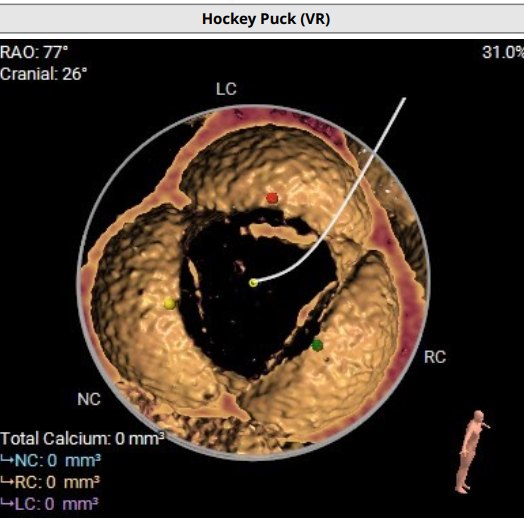

CT评估:三叶式主动脉瓣,无钙化,瓣环27.9mm,窦直径44-46mm。

主动脉根部解剖